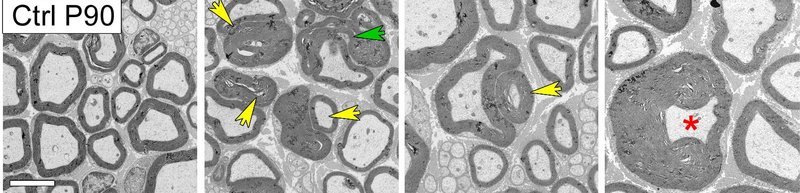

The new finding was that Rab35 binds this lipid phosphatase complex, and therefore plays a key role in regulating myelin sheath formation. The detection was confirmed in knock-out micethat specifically lack the Rab35 protein in Schwann cells – the cells in the peripheral nervous system that form myelin sheaths. Loss of the Rab35 protein led to the abnormalities and, eventually, the degenerative destruction (demyelination) of myelin sheaths in the sciatic nerve.

Sciatic nerves from 3-month-old mice in cross section: In contrast to control animals (on the far left), animals with loss of the Rab35 protein in Schwann cells exhibit demyelination of nerve fibers: myelin outfoldings (yellow arrow); myelin degeneration (green arrow); ‘tomacula’ – focal thickening of the myelin sheath (red star). Image: Alessandra Bolino, IRCCS Ospedale San Raffaele